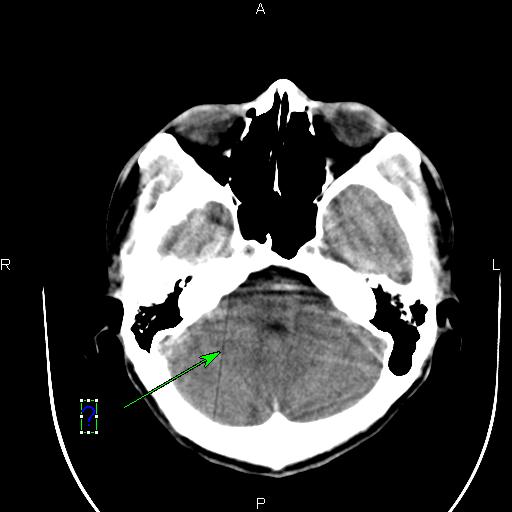

这种伪影是怎样造成的?怎样解决呢?

DAS部份有问题

应该探测器部分。

在扫描分析中检查一下均值 和差值正常否?有无跳变? 应该是通道问题.

是否探测器某通道出现故障?!

应该是某个通道跳起引起的直线伪影。你可以在过滤成像里检查一下,应该可以看到一跟亮线,找到是某个通道,然后屏蔽就可以了。另外一种方法就是,在ps里,不放线,不旋转,之间看所有的通道值,有没有跳起的?在ps里,放线,不旋转,这样可以看得更加清晰!你可以找到跳起的通道,或你也可以找到相应位置的das板,然后把有问题的das板换到边上,这样也可以解决问题。应该是检测器中间部位的某个das板或是通道引起的伪影